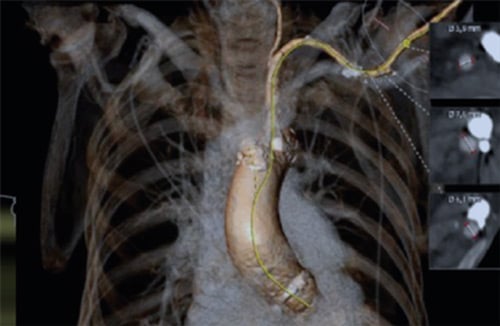

- Prefer left axillary in most cases for a more favorable orientation to the aortic valve; reserve the right axillary artery for cases where the left is unsuitable (Figures 1- 5).

Figure 1: CT scan reconstruction with center line

Figure 4: CT scan reconstruction with dimensions (essential to evaluate for access use)